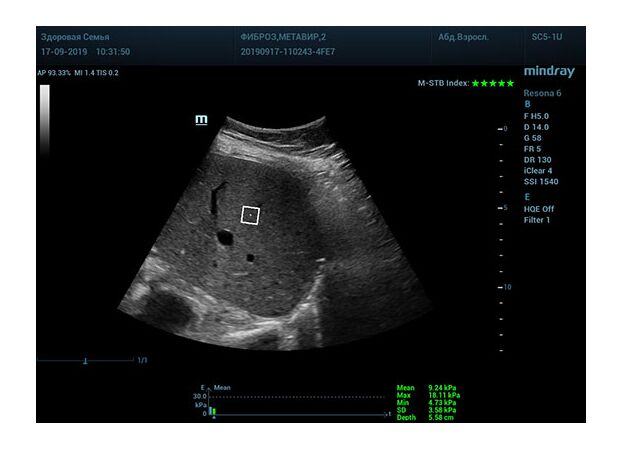

Определение плотности печени. Не ошибся ли оператор при измерении эластических свойств печени? Для оценки критериев качества предусмотрен индекс MBT, который покажет насколько «твердой» была рука оператора и двигалась ли печень. При MBT 5* рука тверда и показатели достоверны. Для оценки качества результатов используется IQR индекс, отображающий колебания показателей в точке измерения при расчете медианы. Показатели при IQR <30% считаются приемлемыми. Техника сканирования через межреберные промежутки требует размещение окна интереса на несколько сантиметром ниже капсулы, для исключения эффекта реверберации. Установка ROI на паренхиму без захвата сосудов, для исключения погрешностей измерения.

Стадия фиброза определяется по системе METAVIR Staging, построенной на данных биопсии и сопоставлении с данными эластографии. Своевременная диагностика фиброза, и начало его лечения, залог благоприятного исхода заболевания.